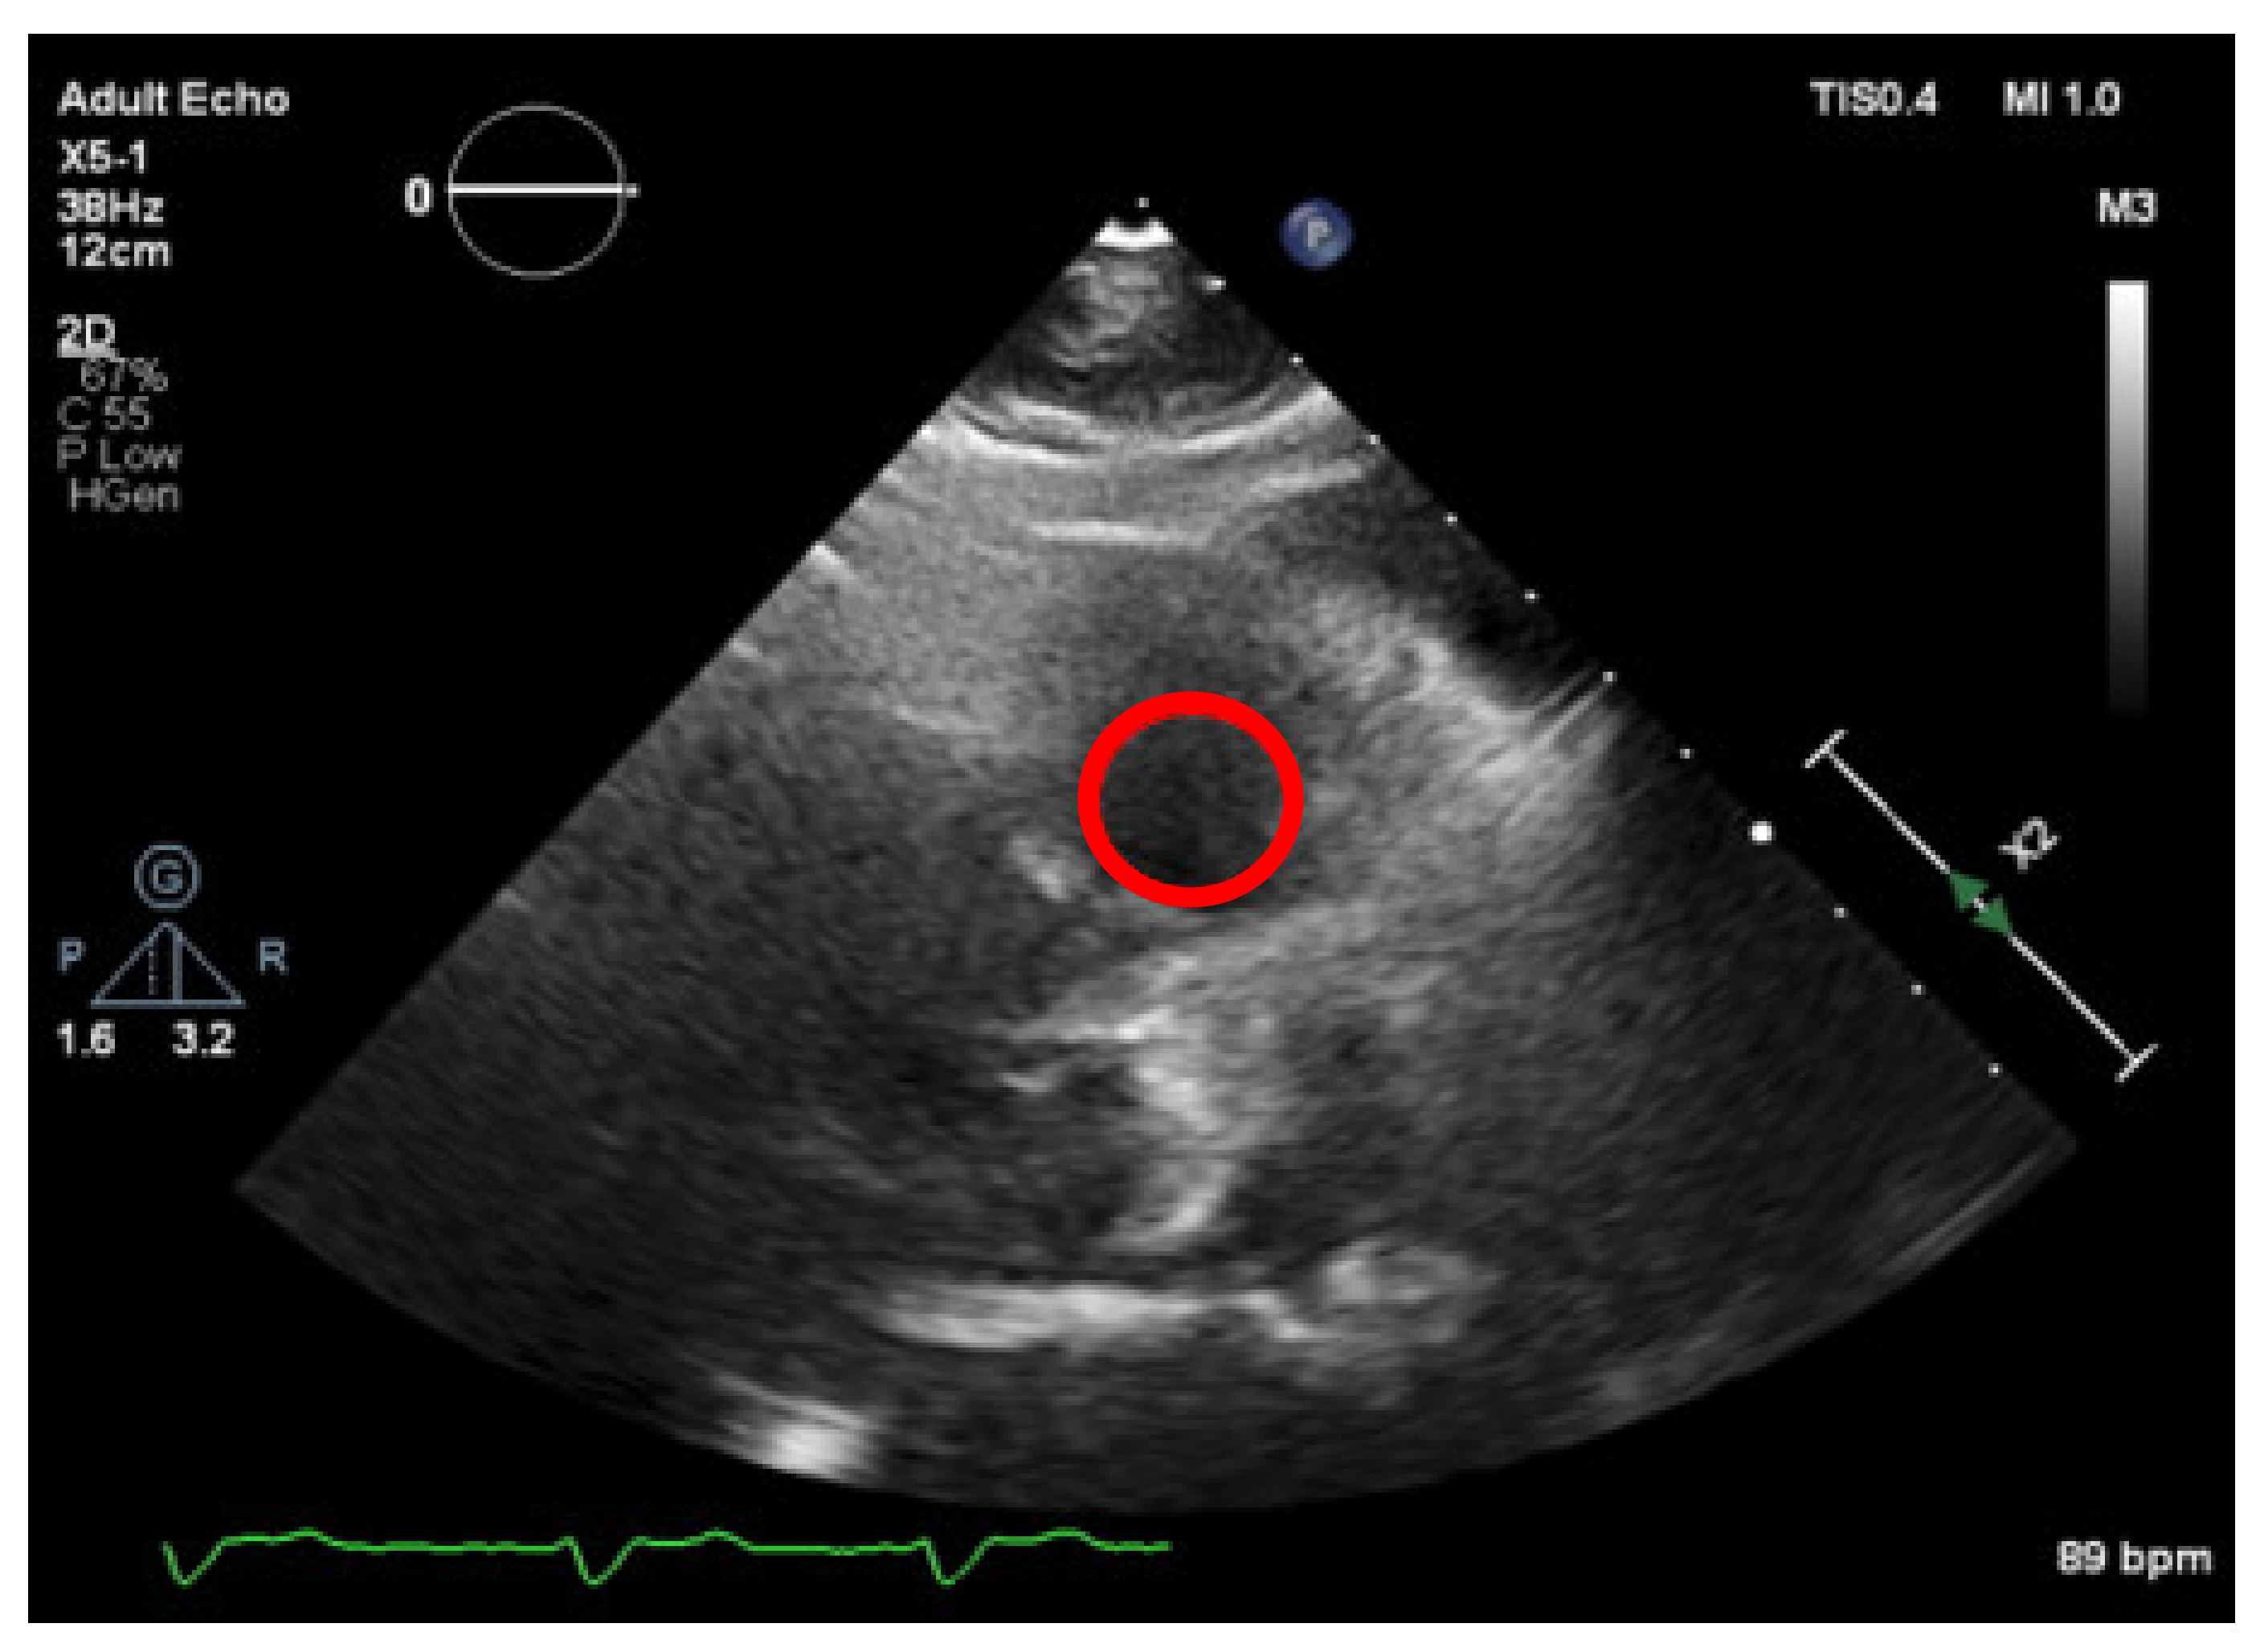

Subsequently, to improve the contrast of e q u a l i z e d x , y , a Contrast Limited Adaptive Histogram Equalization algorithm [19] was implemented that will divide the image into several non-overlapping regions of almost equal sizes, creating several histograms that will redistribute the image brightness, achieving the results in the overall image contrast depicted in Figure 1. To conclude the process, a thresholding technique was used, to segment the image into foreground and background, for further interpretation.

Nevertheless, this simple approach relying solely on histogram equalization leads to poor and inconclusive results in terms of visualizing and extracting the presence of calcium, as shown in Figure 1. The red circle represents where there is calcium on the aortic valve, and in yellow, other structures are marked, which are indistinguishable from each other.

Figure 1. Echocardiography image with CLAHE—The red circle represents the region of interest (ROI) where the calcified aortic valve is located, and in yellow, other structures are marked, which are non-calcified structures.